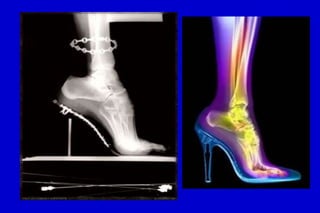

La alta incidencia de estas deformidades en

las mujeres tiene una estrecha vinculación

con el uso de tacón elevado u horma

superestrecha, que mantienen la

articulación MTF en hiperextensión por un

largo período, con la consiguiente

contractura de las estructuras dorsales y el

debilitamiento y relajación de las

estructuras plantares, que se tornan

insuficientes para reequilibrar esa

articulación